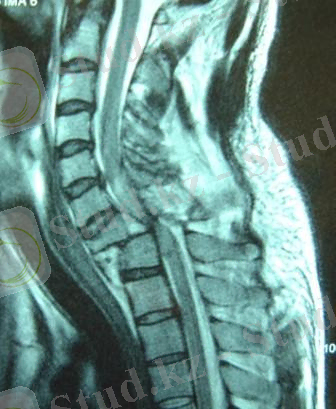

Магнит-резонансты томография (МРТ) омыртқа өзегіндегі жұлын мен түбіршелер және сынған омыртқа фрагменттер қатынасын анықтауға көмектеседі. Бұл әдіс оперативті емге көрсеткішті анықтап, ауру ағымын болжау үшін қажет. Омыртқаның біріншілік асқынбаған сынығы кейін сүйек мүйісіне және екіншілік миело- радикулопатияға асқынады. (рис. 7) .

Рис. 7. MPT жұлын басылып қалуы мен кеуде омыртқасының сынықты шығуы